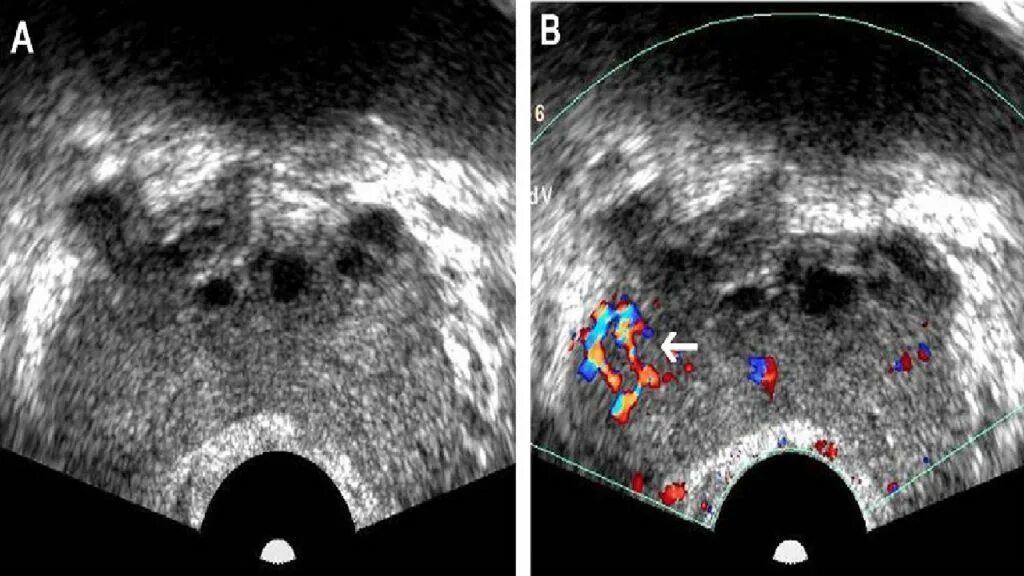

Злокачественная опухоль предстательной железы. Злокачественные новообразования простаты. Генная терапия злокачественных опухолей. Генная терапия в онкологии Карцинома предстательной железы УЗИ. Допплерография предстательной железы. Онкология предстательной железы

Карцинома предстательной железы УЗИ. Допплерография предстательной железы. Онкология предстательной железы Злокачественное новообразование предстательной железы. Карцинома предстательной железы. Susp BL предстательной железы что это. Tumor предстательной железы

Карцинома 4 степени предстательной железы. Онкология предстательной железы. Опухоль предстательной железы стадии Эластография предстательной железы. Компрессионная эластография предстательной железы. УЗИ С эластографией предстательной железы. Образование предстательной железы УЗИ

Эластография предстательной железы. Компрессионная эластография предстательной железы. УЗИ С эластографией предстательной железы. Образование предстательной железы УЗИ Опухоль предстательной железы. Злокачественное новообразование предстательной железы. Карцинома предстательной железы. Tumor предстательной железы

Предстательная железа у мужчин. Представительна яжелеза. Опухальпредседательнойжелезы Трансректальное УЗИ предстательной железы. УЗИ трузи предстательной железы. Карцинома предстательной железы УЗИ. Опухоль предстательной железы УЗИ

Трансректальное УЗИ предстательной железы. УЗИ трузи предстательной железы. Карцинома предстательной железы УЗИ. Опухоль предстательной железы УЗИ Массажер для аденомы простаты. Массаж предстательной железы мужчинам

Образование предстательной железы УЗИ. УЗИ предстательной железы РПЖ. Диагностика опухолей предстательной железы

Образование предстательной железы УЗИ. УЗИ предстательной железы РПЖ. Диагностика опухолей предстательной железы Злокачественное новообразование предстательной железы. Онкозаболевания предстательной железы. Аденома простаты злокачественная. Мкб предстательной железы